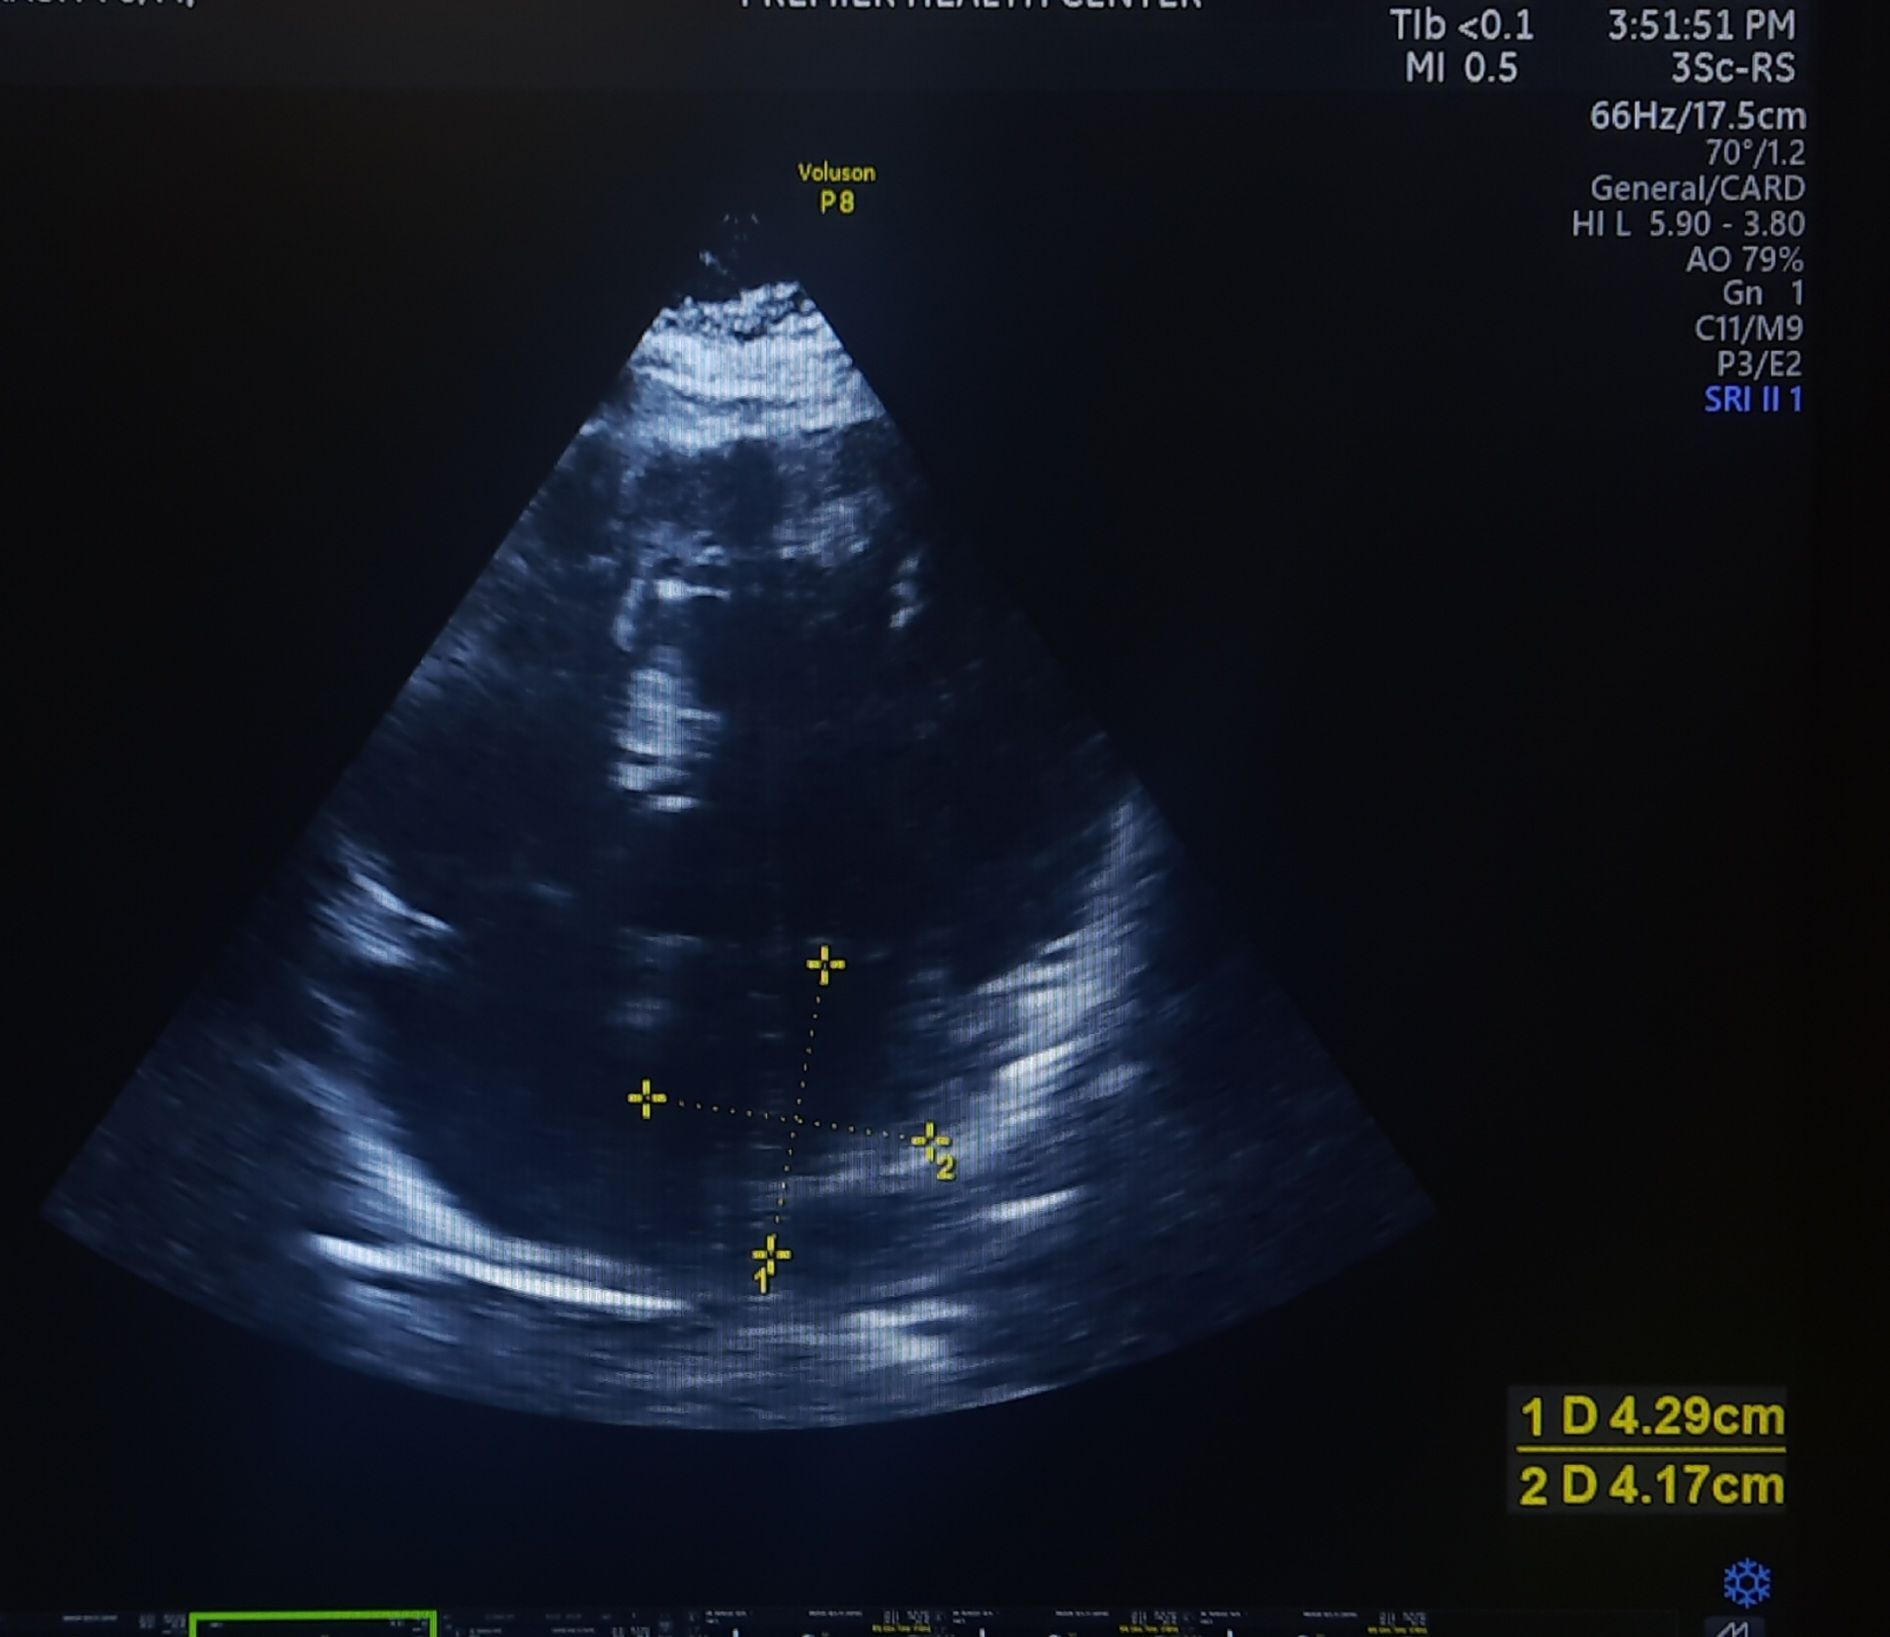

I saw two patients recently, with a similar degree of hypertension and LVH. One with a normal-sized LA and the other with a mild LA enlargement.

When checked for the “E” declaration time, it was found to be absolutely normal in the patient who had LAE. The one with normal LA size had a relatively short DT and his functional capacity was less.

52-year-old man with HT, and LVH with mild LAE. His E DT was very much normal a1 178 ms. He has a good functional capacity. I expected a grade 2 diastolic dysfunction. But, none of the other parameters were convincing. Used to think, if LA is enlarged, it must be a little advanced form of diastolic dysfunction. Though It is still true in many, but, this case, demand us to dwell into these two important parameters of LV diastolic function.

What is the relationship between Left atrial size and Mitral “E” decceleration time ?

Mitral E velocity deceleration time (DT) is a measure derived from Doppler echocardiography, representing the time it takes for the early diastolic filling velocity (E wave) to decline from its peak to baseline.

In healthy individuals with normal LA size and normal diastolic function, DT is typically within a normal range (e.g., 160–240 ms), and LA size does not significantly influence DT. In pathological states, an enlarged LA (e.g., LA volume index >34 mL/m²) combined with a shortened DT (<160 ms) indicate restrictive physiology or advanced diastolic dysfunction.